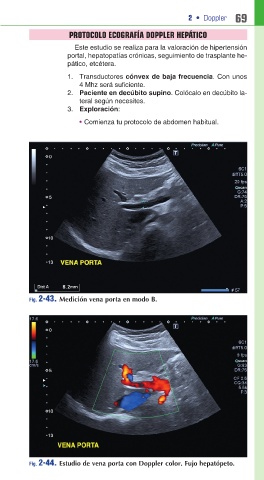

Fig. 2-43. Medición vena porta en modo B.

Fig. 2-44. Estudio de vena porta con Doppler color. Fujo hepatópeto.